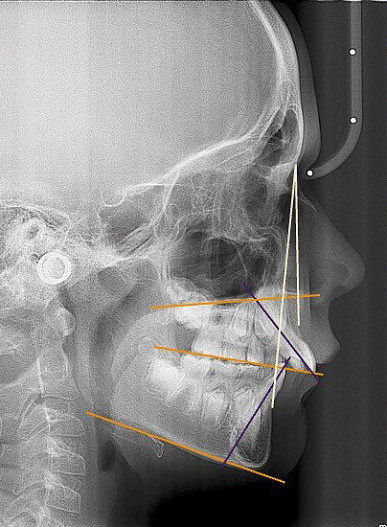

Neunjähriger Patient mit deutlich vergrößertem Overjet aufgrund eines Distalbisses in Kombination mit einer Protrusion der Oberkieferfront. Habits bzw. myofunktionelle Aspekte wurden adressiert. Die Behandlung erfolgte mit einem Invisalign-Schienensatz (56 Aligner) mit Precsion Wings im Rahmen einer Frühbehandlung zur Prophylaxe eines Frontzahntraumas.

Klinisches Fallbeispiel 2 (Abb. 2a–y)

Distalbiss und tiefer Biss bei einem zwölfjährigen Mädchen. Die Behandlung erfolgte mit Invisalign und Precision Wings. Insgesamt waren zwei Schienensätze notwendig. Die Gesamtbehandlung dauerte 18 Monate.Bei der Planung des ClinCheck wurde der tiefe Biss vorwiegend über eine Intrusion der Unterkieferfront behoben, um die Lachlinie der Patientin nicht negativ zu beeinflussen. Die Oberkieferfront wurde nur retrudiert, jedoch vertikal nicht intrudiert. Während der Phase des Mandibular Advancement wurde die Wirkung der Precision Wings durch den Einsatz von Klasse II-Gummizügen unterstützt. Schlussendlich wurde auch der hängenden Okklusionsebene durch eine einseitige Intrusion der Molaren im ersten Quadranten Rechnung getragen.